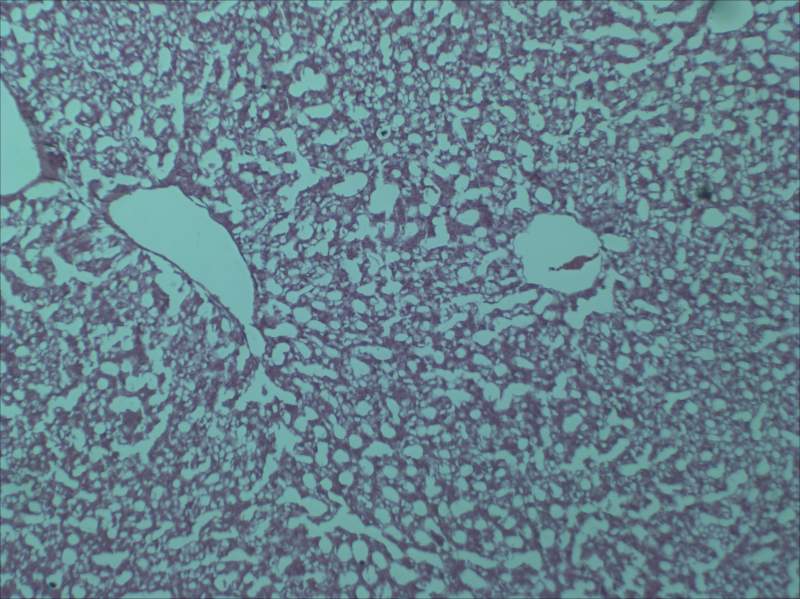

µÚÒ»ÕÅÊÇÈ¥Äê×öµÄ³¦µÀÇÐÆ¬£¬È¾É«Ð§¹û»¹²»´í¡£

µÚ¶þÕÅÊǽñÄê×öµÄ³¦µÀÇÐÆ¬£¬È¾É«ÊÇÕâ¸öÑù×Ó£¬Ôõô¿´¶¼²»¶Ô£¬´óÖ¿ÉÒÔ¿´³ö³¦µÀµÄ½á¹¹£¬µ«Êǵ½´¦¶¼ÊÇ¿ÕÅÝ£¬²»Ã÷°×µ½µ×ÊÇʲôÇé¿ö¡£

µÚÈýÕÅÊǽñÄê×öµÄ¸ÎÔàÇÐÆ¬£¬È¾É«Ò²ÊÇÕâ¸öÑù×Ó¡£